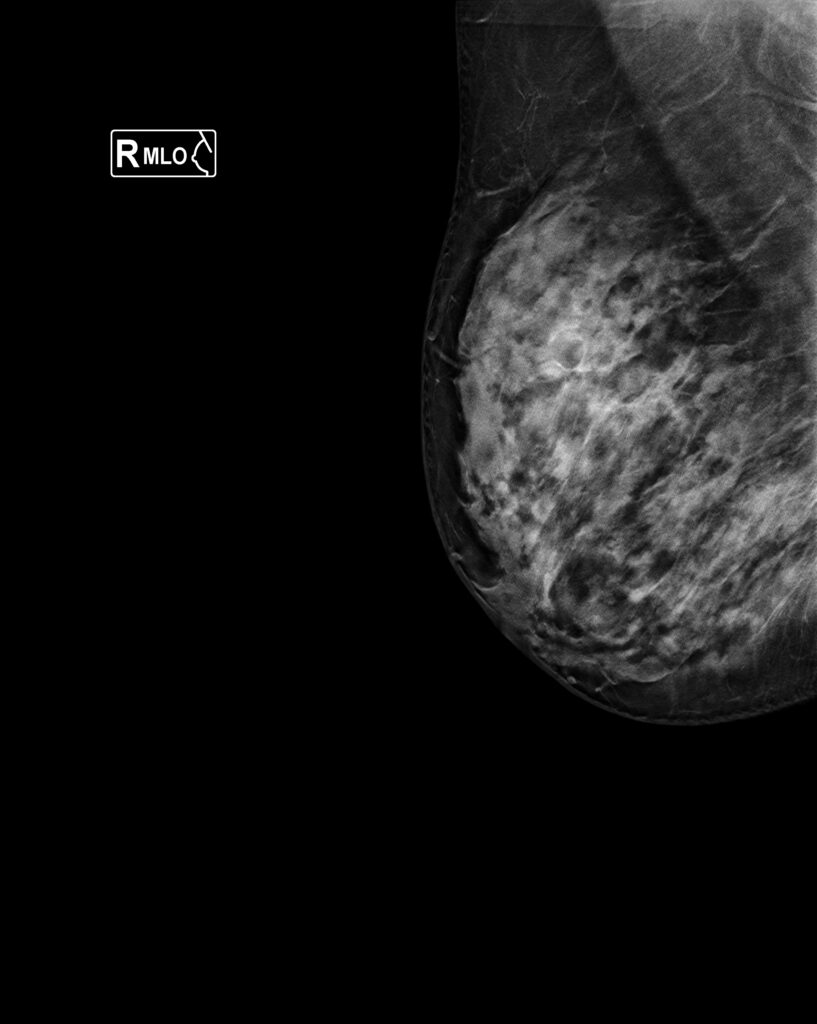

Tipos de estudio mamografico

CATEGORIAS BIRADSv2025